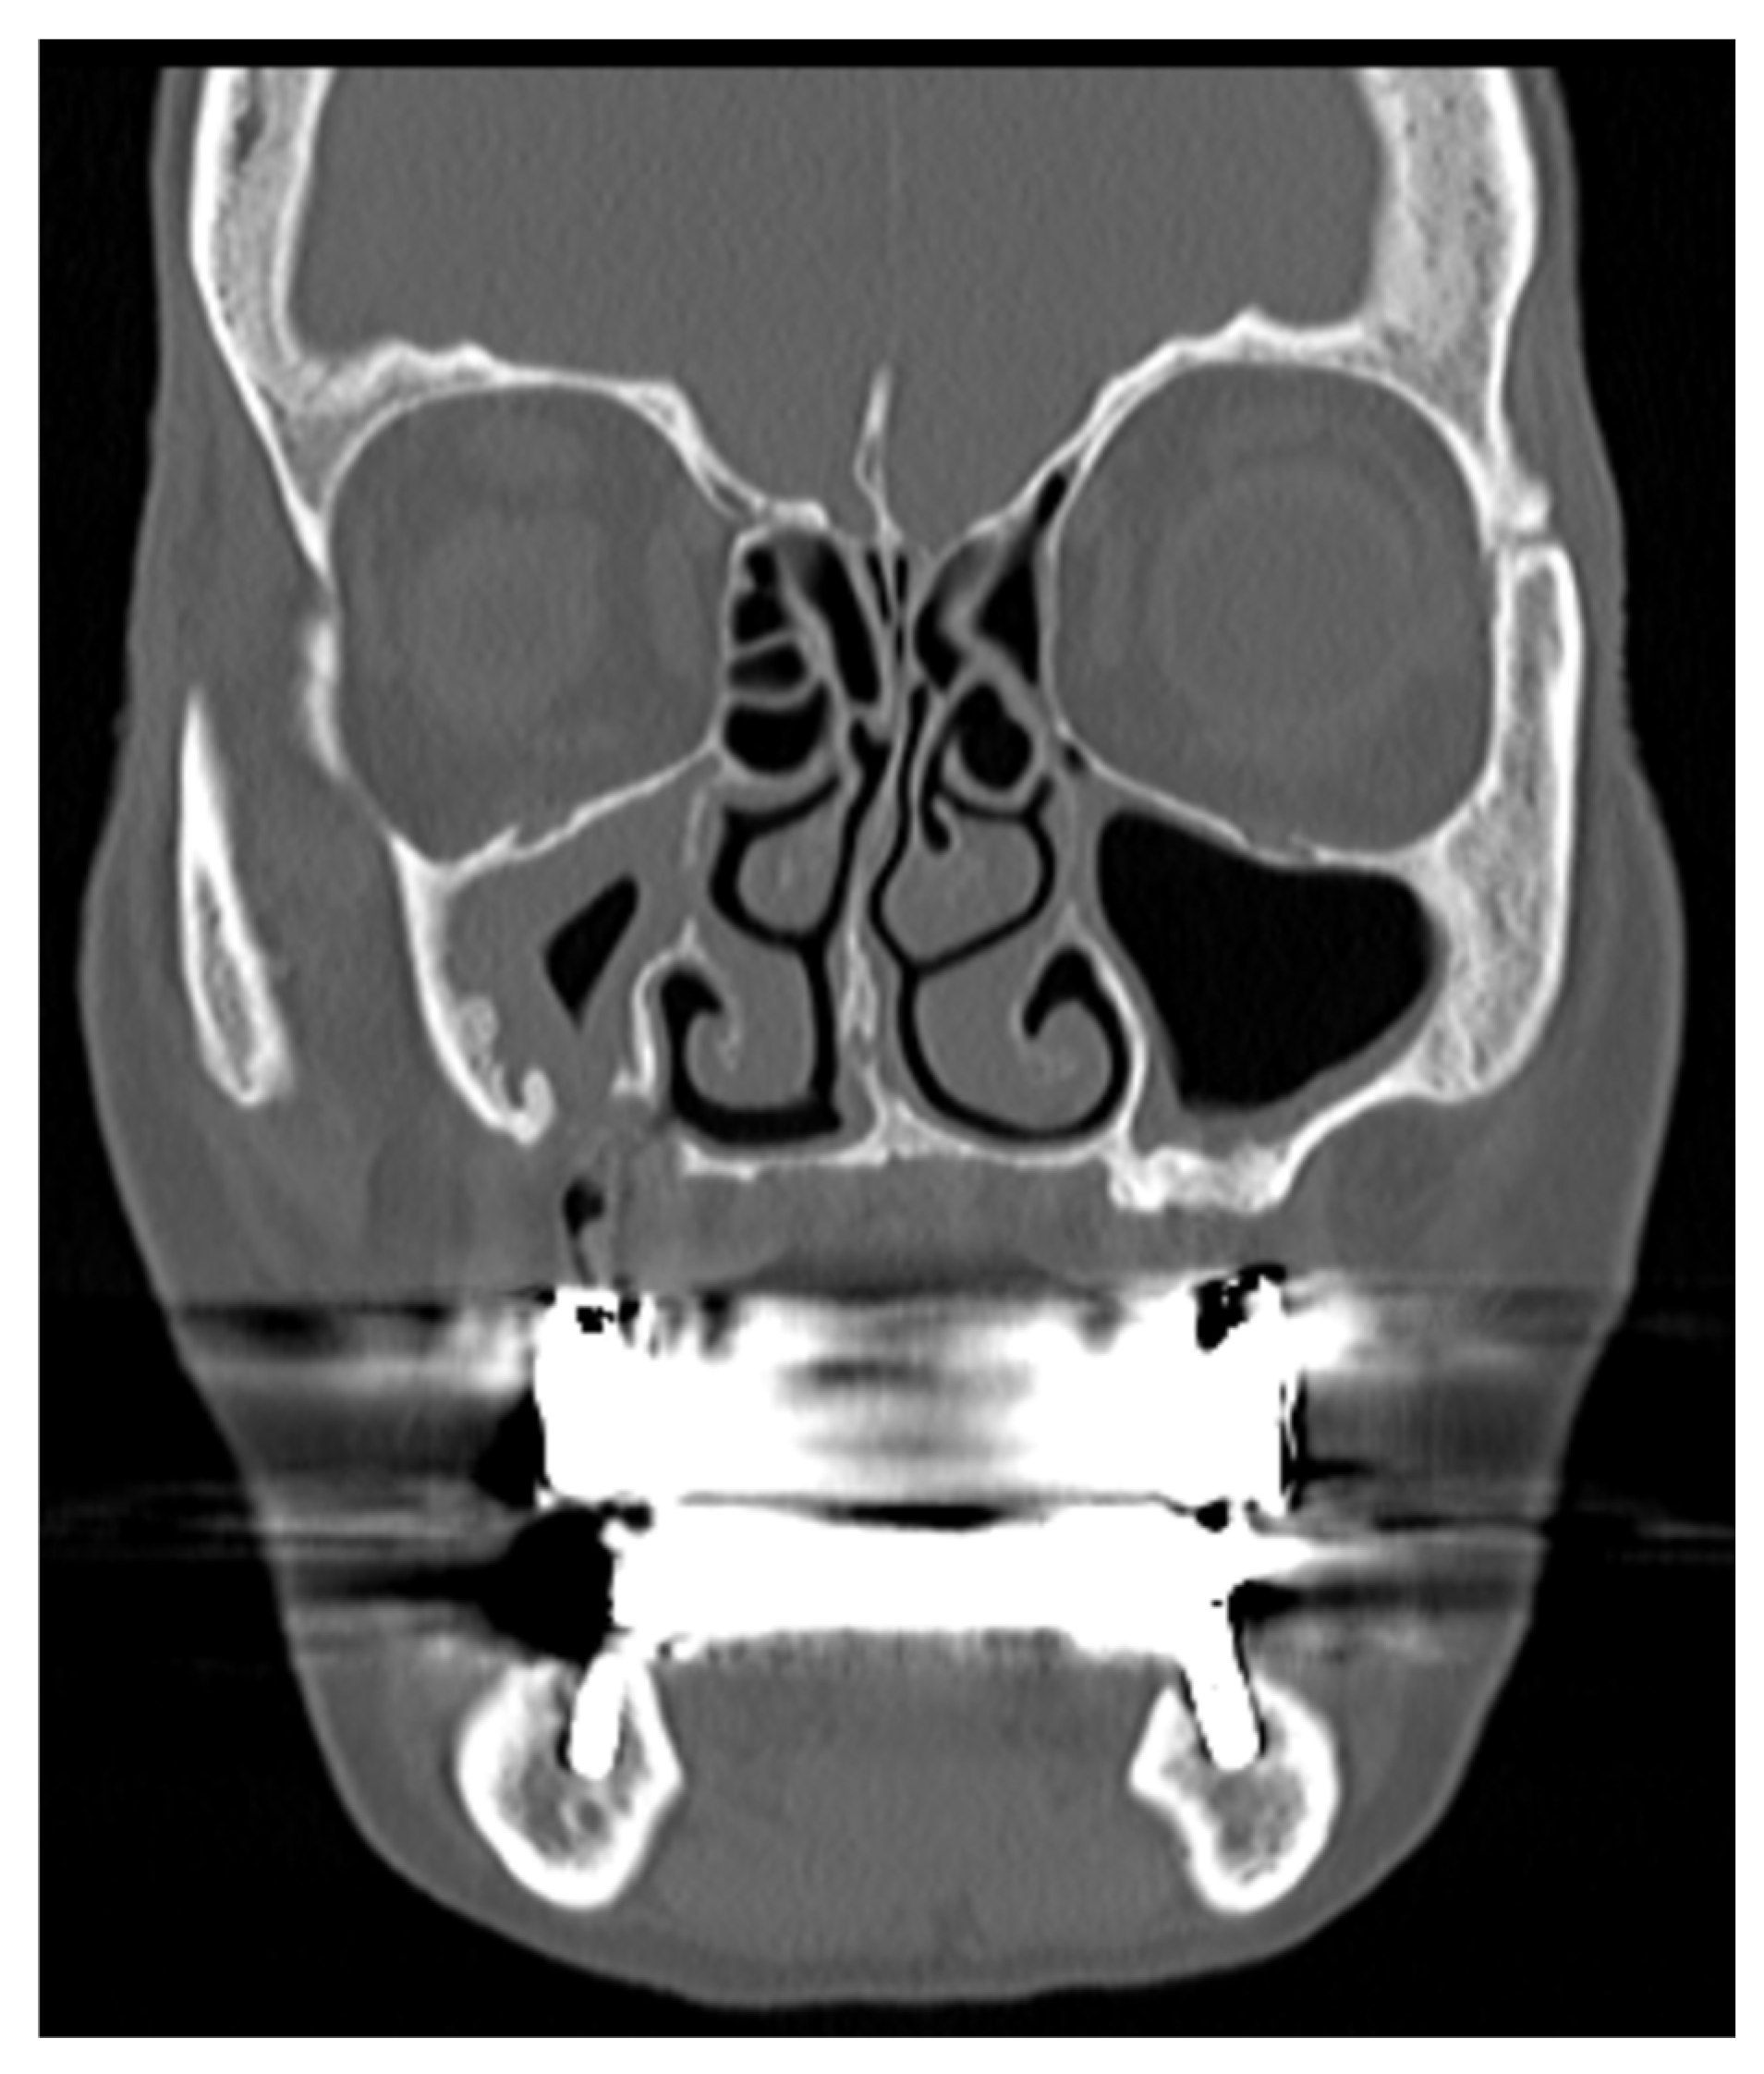

• A patient with chronic sinusitis as complication of dental pathology, with foreign body in the maxillary sinuses, without obstruction of the OMC and with OAF, can be identified as: TcEcB1O0F1 [Figure 4]

Figure 4. Slice TC of patient with TcEcB1O0F1.